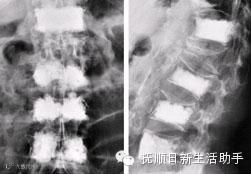

脊柱骨折

应由3~4人在同一侧同时托住伤员的头、肩、臀和下肢,把伤员平托起来,平卧在木板上,并用绷带加以固定。伤者最好取俯卧位,并在胸腹部放一软枕。严禁采用“搬头搬脚”的抬抱方式移动或搬运伤者,也禁用普通的软担架搬运。